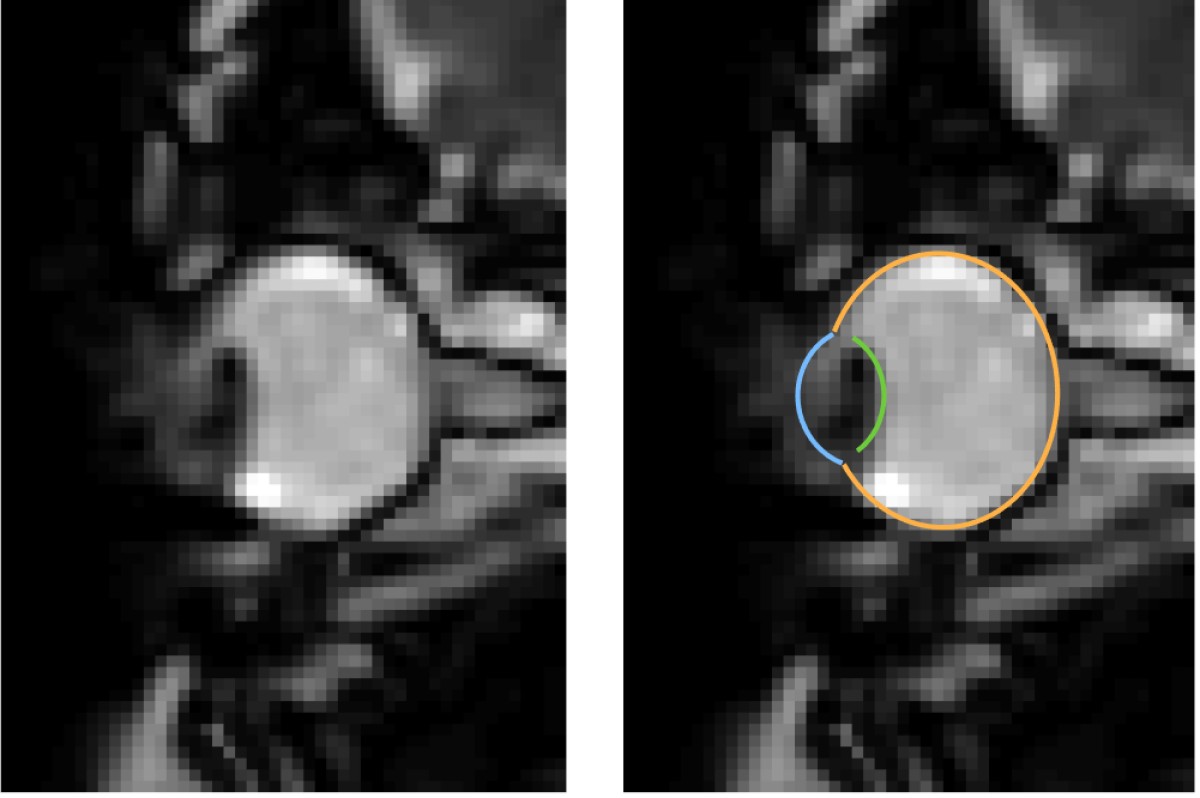

MRI images of eye movements during blinking: The eye is pulled back into the eye socket. The left image shows only the dynamic MRI data, the right image additionally shows the segmentation of the eye by the MREyeTrack. The photo corner consisting of six images shows the eye movement.© WWU - Johannes Kirchner

Eye movements are typically measured using eye-trackers, which are high speed cameras that film pupil position.” We were able to develop a method that captures eye movements in unprecedented temporal resolution using real-time MRI. Using this new method, we could show that the whole eyeball is being pulled back into the eye socket during a blink“, explains author Johannes Kirchner, research assistant at the Institute of Psychology at Münster University. The scientists from the University of Münster developed the method with co-author Prof. Tamara Watson from Western Sydney University.

MRI is a relatively slow procedure, the temporal resolution usually ranges between seconds or minutes. Eye movements on the other hand are fast and typically last only a few dozen milliseconds. Recent technological advances allowed the recording of 2-D MR images at a resolution of up to 20 milliseconds. Those ultrafast MR sequences were initially developed for cardiac imaging and haven’t been applied to the recording of eye movements. “We could reach a temporal resolution of 35 milliseconds. Total scan duration of only a few minutes already leads to the acquisition of over 10000 images. For actual eye-tracking, a fully automatic segmentation algorithm to analyse these images was needed”, explains co-author Prof. Markus Lappe, professor for cognitive neuroscience at the Institute of Psychology at the University of Münster. “With ‘MREyeTrack’ we have developed such a segmentation algorithm, which allows the fully-automated analysis of eye position and orientation in every single image.”